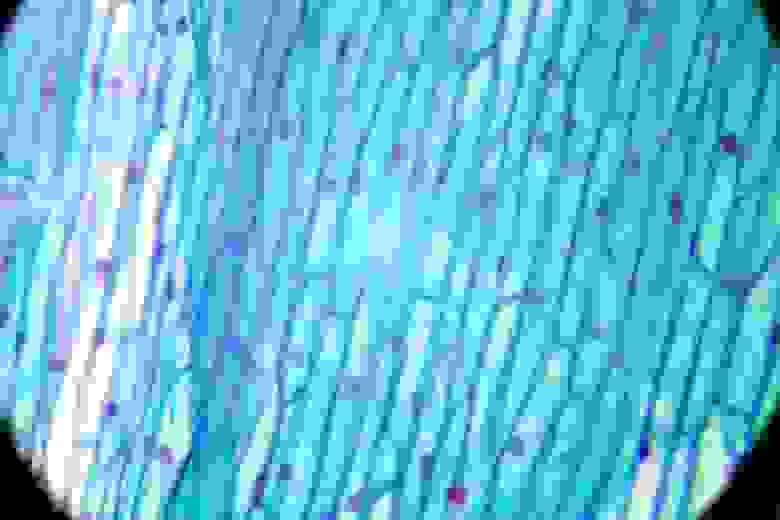

Берцовая кость человека:

Печать лазерным принтером: